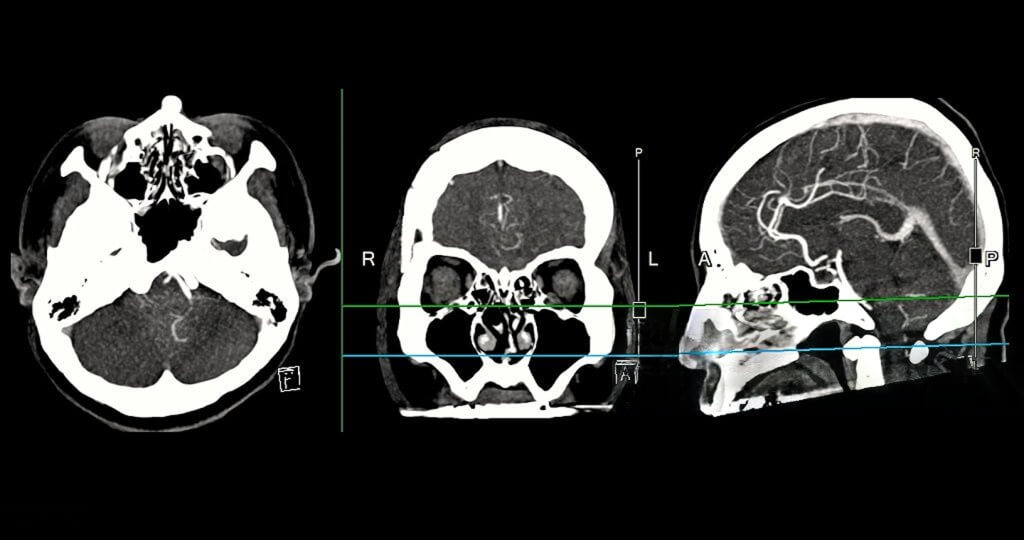

A CT (Computed Tomography) scan is an advanced medical imaging procedure that uses X-rays and computer processing to create highly detailed cross-sectional images of the body. Unlike a regular X-ray, which mainly shows bones, a CT scan can clearly visualize soft tissues, blood vessels, bones, and internal organs, helping doctors detect a wide range of conditions.

A contrast-enhanced CT scan that visualizes blood vessels in detail, helping detect blockages, narrowing, or other vascular abnormalities in arteries and veins.

A technique that converts 2D scan data into three-dimensional models of internal structures, allowing doctors to view anatomy from multiple angles for better diagnosis and surgical planning.